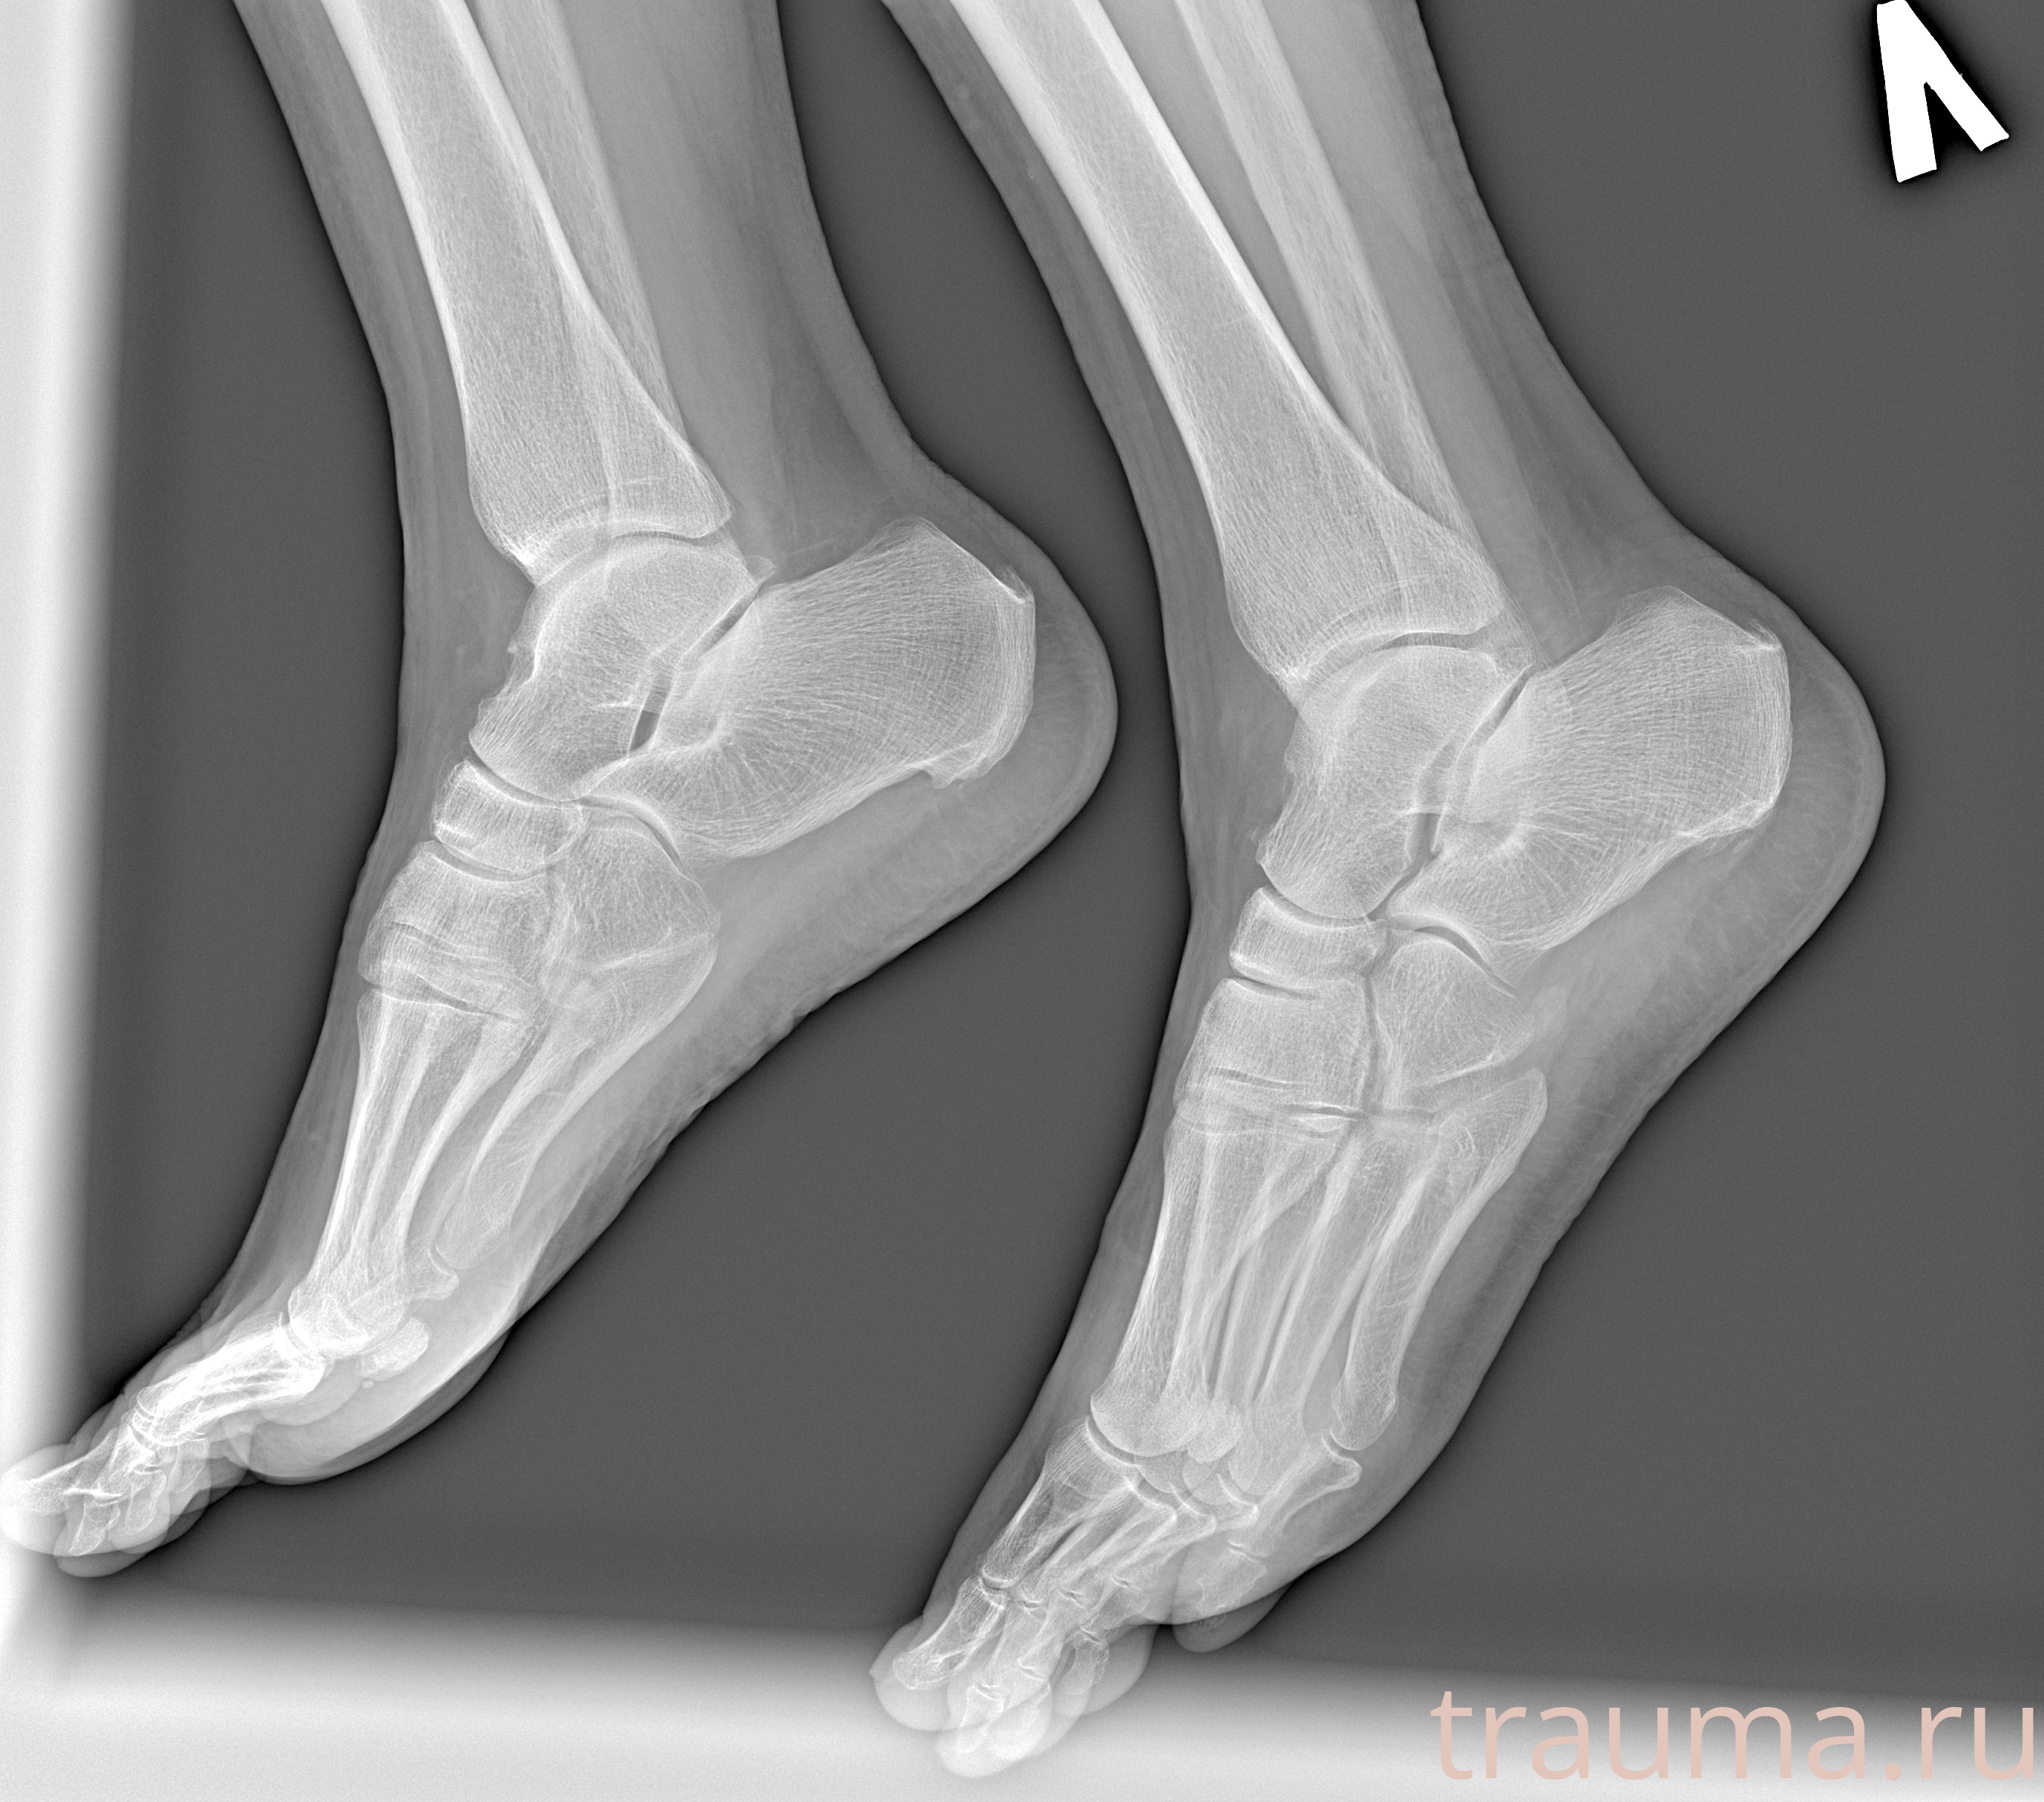

Рентгенограммы

Рентген на дому: по вашему адресу приезжает врач-рентгенолог, травматолог-ортопед с мобильным рентгеновским аппаратом, проводит диагностику травмы или заболевания, делает необходимые рентгенограммы, дает рекомендации по дальнейшему лечению. Получить качественные снимки в домашних условиях возможно благодаря уникальной методике, разработанной МосРентген Центром для института  Склифосовского